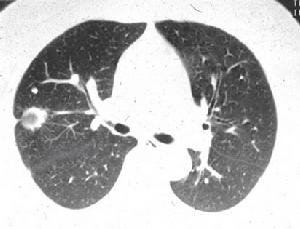

熱盛迫血證熱盛迫血證對照組肺臟表面光滑,呈粉紅色,彈性良好。模型組肺臟略呈暗紅色,可見明顯的瘀斑,部位猶以前部及下部為多。養陰生津方組病變程度較輕,僅見少數散在瘀點。